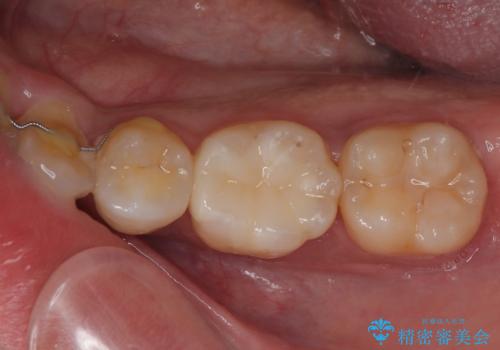

銀歯の下の虫歯を治したい オールセラミッククラウン・セラミックインレー修復